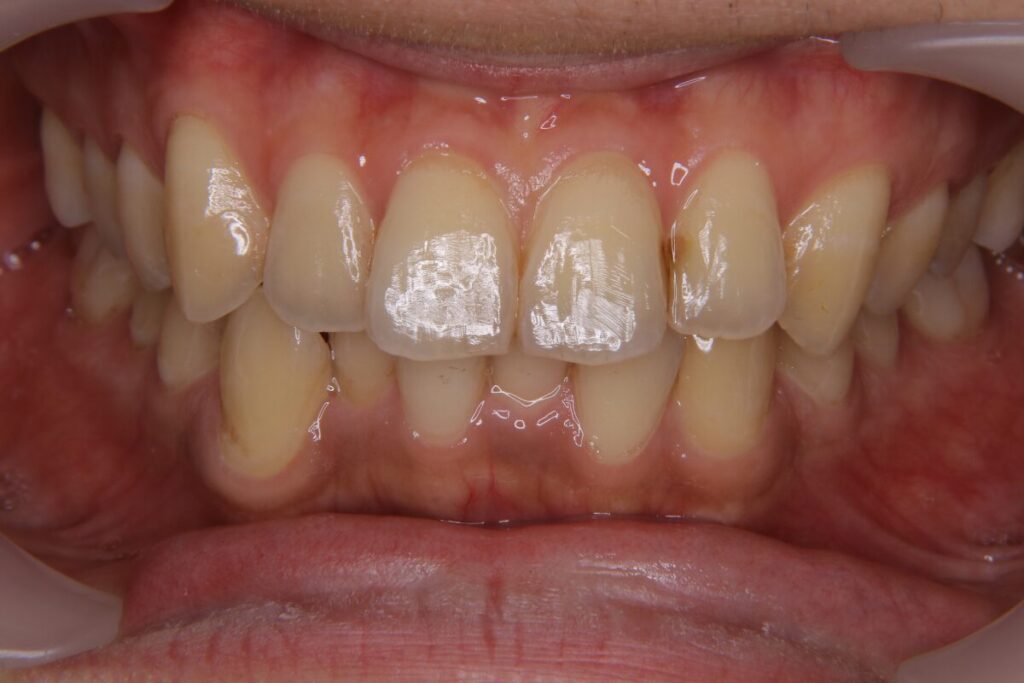

| 患者 | 44歳男性 |

|---|---|

| 主訴 | 前歯のガタガタ、ねじれ |

| 診断名 | U1翼状捻転を伴うAngle I級症例 |

| 治療内容 | マウスピース型矯正装置(インビザライン) |

| 抜歯の有無 | 非抜歯 |

| 治療期間 | 6か月 |

| 費用(税込) | 495,000円 |

| リスクと副作用 | 痛み等、歯根吸収/歯肉退縮、後戻り、むし歯・歯肉炎の可能性。 |

【医師コメント】

前歯のねじれが気になり来院された患者さんです。

奥歯の前後関係はAngleⅠ級で大きなズレはなく、主な課題は前歯(U1)の捻転でした。

そのため、歯の回転と前歯の並びを整えることを目的に、非抜歯のマウスピース型矯正装置(インビザライン)が適応と判断しました。

装着状況も良好で、計画通りに回転をコントロールし、6か月で前歯の捻転と歯列のラインを整えることができました。マウスピースの枚数が少ないプランだったため、費用も抑えて治療をすることができました。